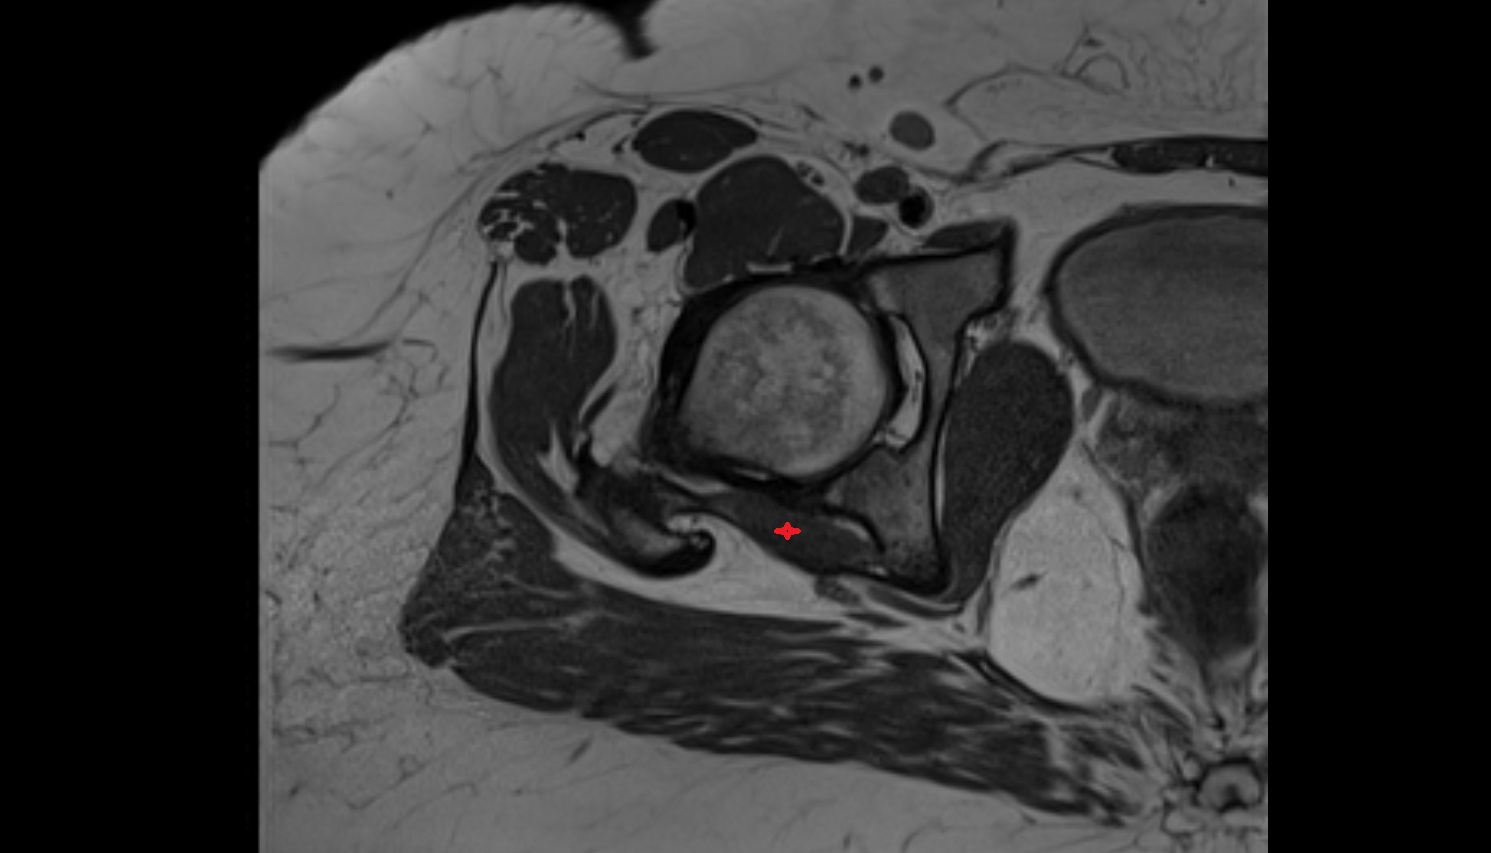

- Hip joint